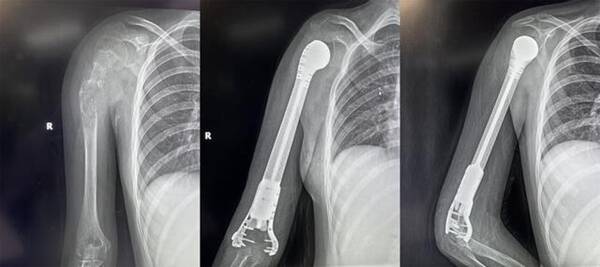

2022419日,西安市紅會醫(yī)院骨病腫瘤科為一名13歲小患者成功實施了肱骨惡性腫瘤切除3D打印假體重建術。

對于一個13歲的女孩來說,截肢必然會對孩子的心靈帶來巨大陰影,同時小欣父母表達了強烈的保肢意愿后,最終決定選擇保肢方案。針對小欣的具體病情,骨病腫瘤科楊團民主任帶領團隊成員王志酬、黃桂林、邵宇雄、李爭爭主治醫(yī)師等人,經過認真病例討論,決定新輔助化療后,手術切除右肱骨骨腫瘤。發(fā)揮3D打印在骨科領域優(yōu)勢,設計個體化3D打印肱骨上段鈦合金假體,結合人工肩關節(jié)技術,保留部分正常骨、患肢長度,可實現(xiàn)肱骨重建。

術前,經精密計算機輔助設計、影像學數(shù)據鏡像反求和鈦合金3D打印,假體的3D打印仿骨小梁端和截骨端可以完美貼合,使骨長入得以實現(xiàn),達到生物重建效果。這樣既保留了關節(jié),也減少假體松動的發(fā)生率。同時空隙結構利于軟組織長入。手術當日,在麻醉科配合下,楊團民主任團隊密切協(xié)作、精細操作,依次完成腫瘤切除、3D打印假體植入、軟組織重建系列操作。歷時3小時,順利完成醫(yī)院首例3D打印肱骨假體治療肱骨骨肉瘤手術。